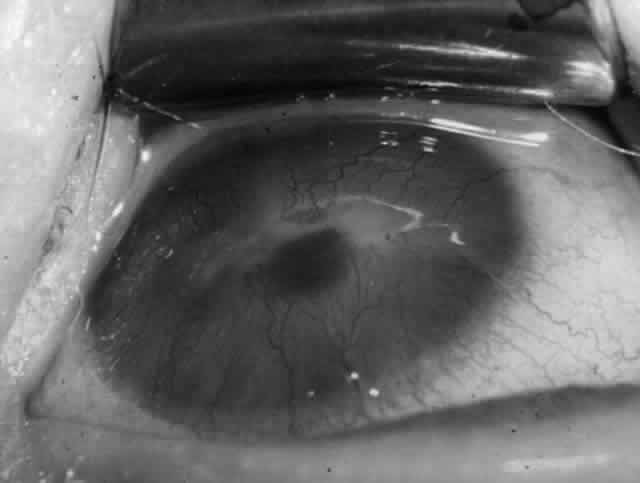

Clinically, the ocular disease in cicatricial pemphigoid (OCP) may present unilaterally in the form of a chronic, recurrent catarrhal conjunctivitis, but it eventually becomes bilateral. Subepithelial fibrosis is characteristic of stage 1 of OCP (Fig. 7). Stage 2 shows fornix foreshortening (Fig. 8), and symblepharon formation is the hallmark of stage 3 (Fig. 9). Stage 4, end-stage disease, is characterized by ankyloblepharon and surface keratinization (Fig. 10). Obstruction of the lacrimal ductules and meibomian gland ducts eventually produces an unstable tear film and progressive sicca syndrome, but it is to be emphasized that OCP is not a dry-eye syndrome until late in the disease course.20 Trichiasis and entropion occur because of the subepithelial fibrosis, with eventual keratopathy, corneal neovascularization, and corneal ulceration and scarring.20

Fig. 7. Stage 1 cicatricial pemphigoid, with cicatrizing conjunctivitis, and fine striae-type areas of subepithelial fibrosis, but without evidence of shrinkage of the conjunctiva.